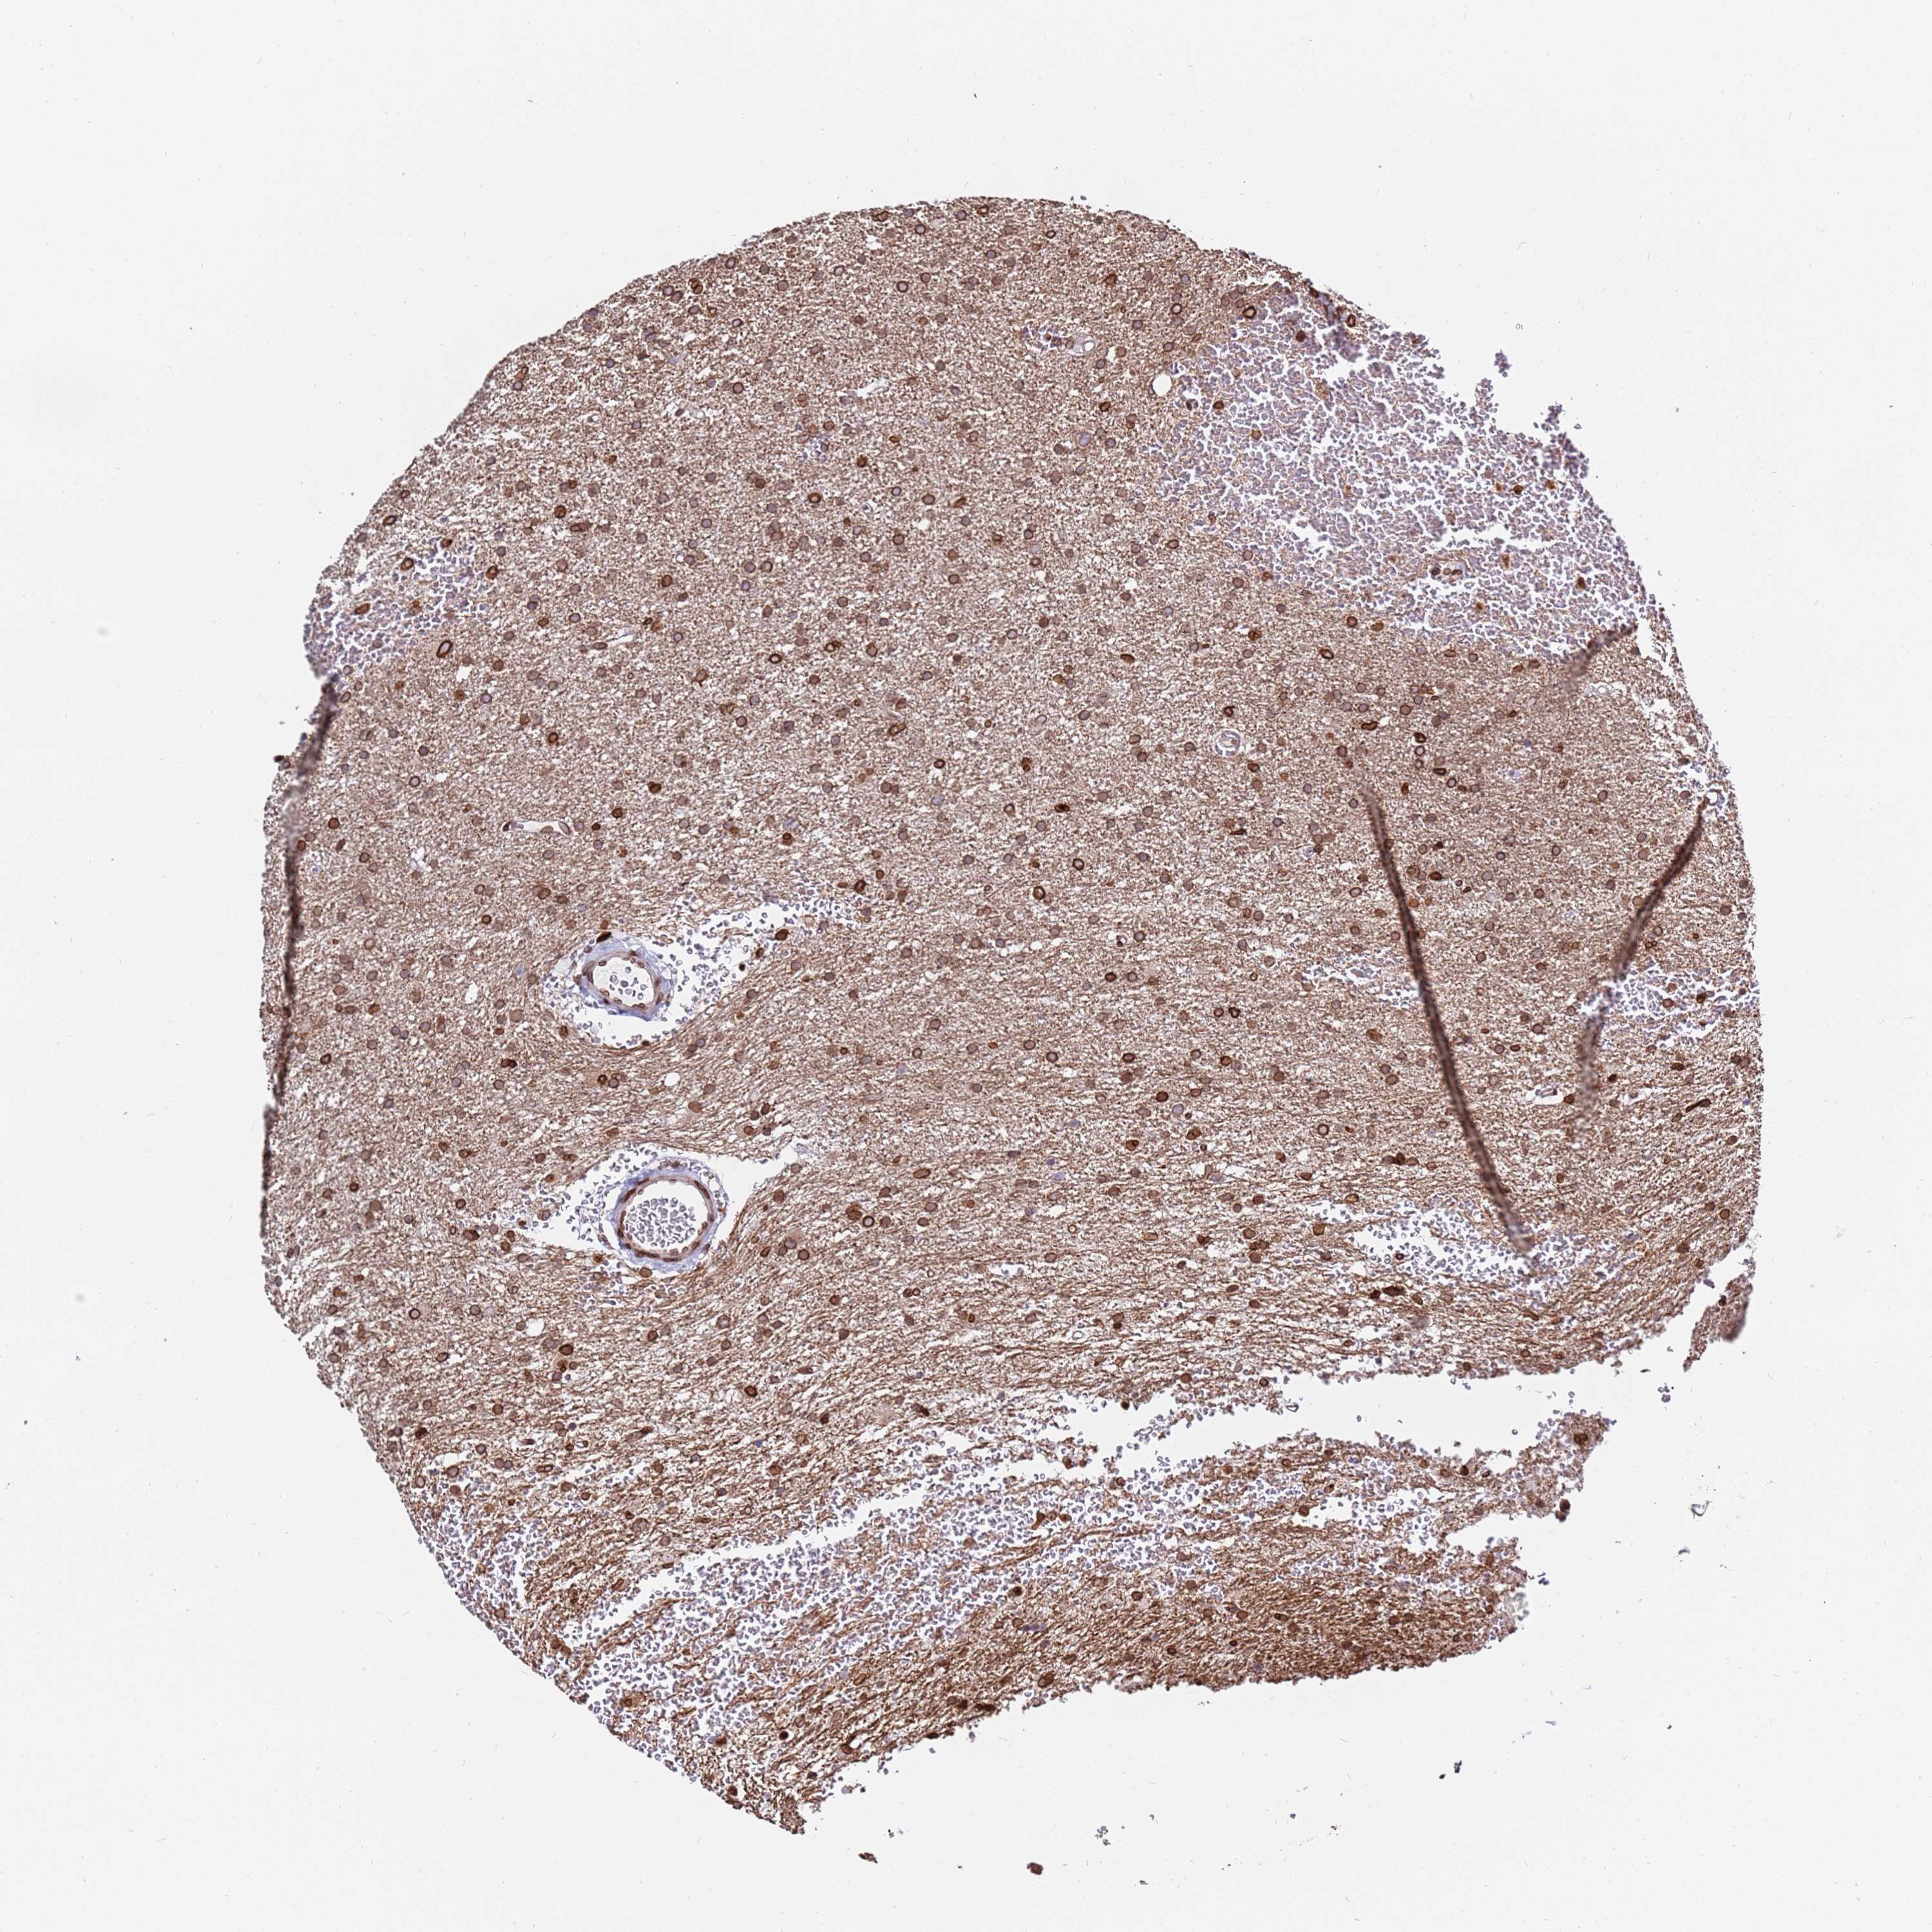

GLIOMA - Protein expressioni

A mouse-over function shows sample information and annotation data. Click on an image to view it in a full screen mode. Samples can be filtered based on level of antibody staining by selecting one or several of the following categories: high, medium, low and not detected. The assay and annotation is described here.

Note that samples used for immunohistochemistry by the Human Protein Atlas do not correspond to samples in the TCGA dataset.

Antibody stainingi

Antibody staining in the annotated cell types in the current human tissue is reported as not detected, low, medium, or high, based on conventional immunohistochemistry profiling in selected tissues. This score is based on the combination of the staining intensity and fraction of stained cells.

Each image is clickable and will lead to virtual microscopy that enables deeper exploration of all samples and also displays staining intensity scores, fraction scores and subcellular localization as well as patient and tissue information for each sample.

Antibody HPA047151

Antibody HPA050546

Antibody HPA070991

Staining

High

Medium

Low

Not detected

Intensity

Strong

Moderate

Weak

Negative

Quantity

>75%

75%-25%

<25%

None

Location

Nuclear

Cytoplasmic/membranous

Cytoplasmic/membranous,nuclear

Glioma, malignant, High grade

Glioma, malignant, Low grade